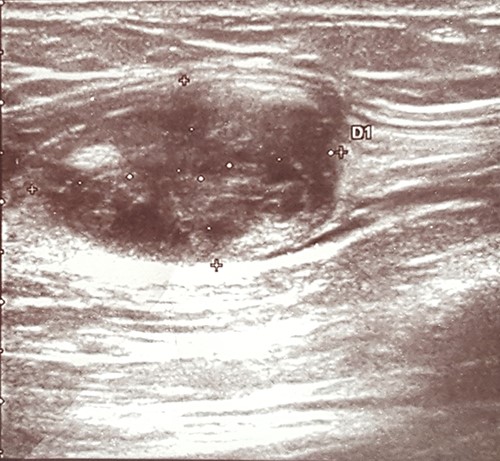

An ultrasound scan revealed a 2.0 × 2.0 cm well-defined heteroechogenic lesion with a cystic component in the left biceps brachii muscle (Fig. 1).

Imaging techniques may include X-ray, ultrasound, computed tomography (CT scan) or magnetic resonance imaging (MRI). X-ray examinations may be normal or show a non-specific intramuscular mass that rarely contains calcifications [4, 12]. On ultrasound images, an IM typically appears as a well-circumscribed, hypoechogenic or heteroechogenic mass, sometimes with a cystic component [1, 11]. CT examinations usually show a well-defined, homogenous, low-density lesion [1–3]. On MRI images, an IM typically presents as a hypointense signal mass on T1-weighted images and with a hyperintense signal on T2-weighted images [3]. In the case reported herein, the ultrasound examination thus showed typical findings of an IM in the form of a well-defined, heteroechogenic lesion with a cystic component. No other imaging studies were performed.